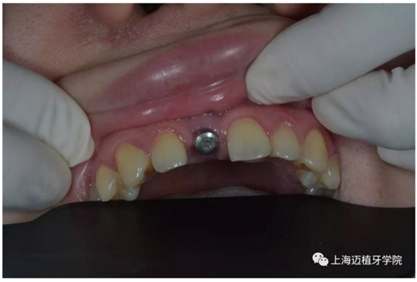

3月后恢復(fù)良好,上愈合基臺

2周后袖口成形